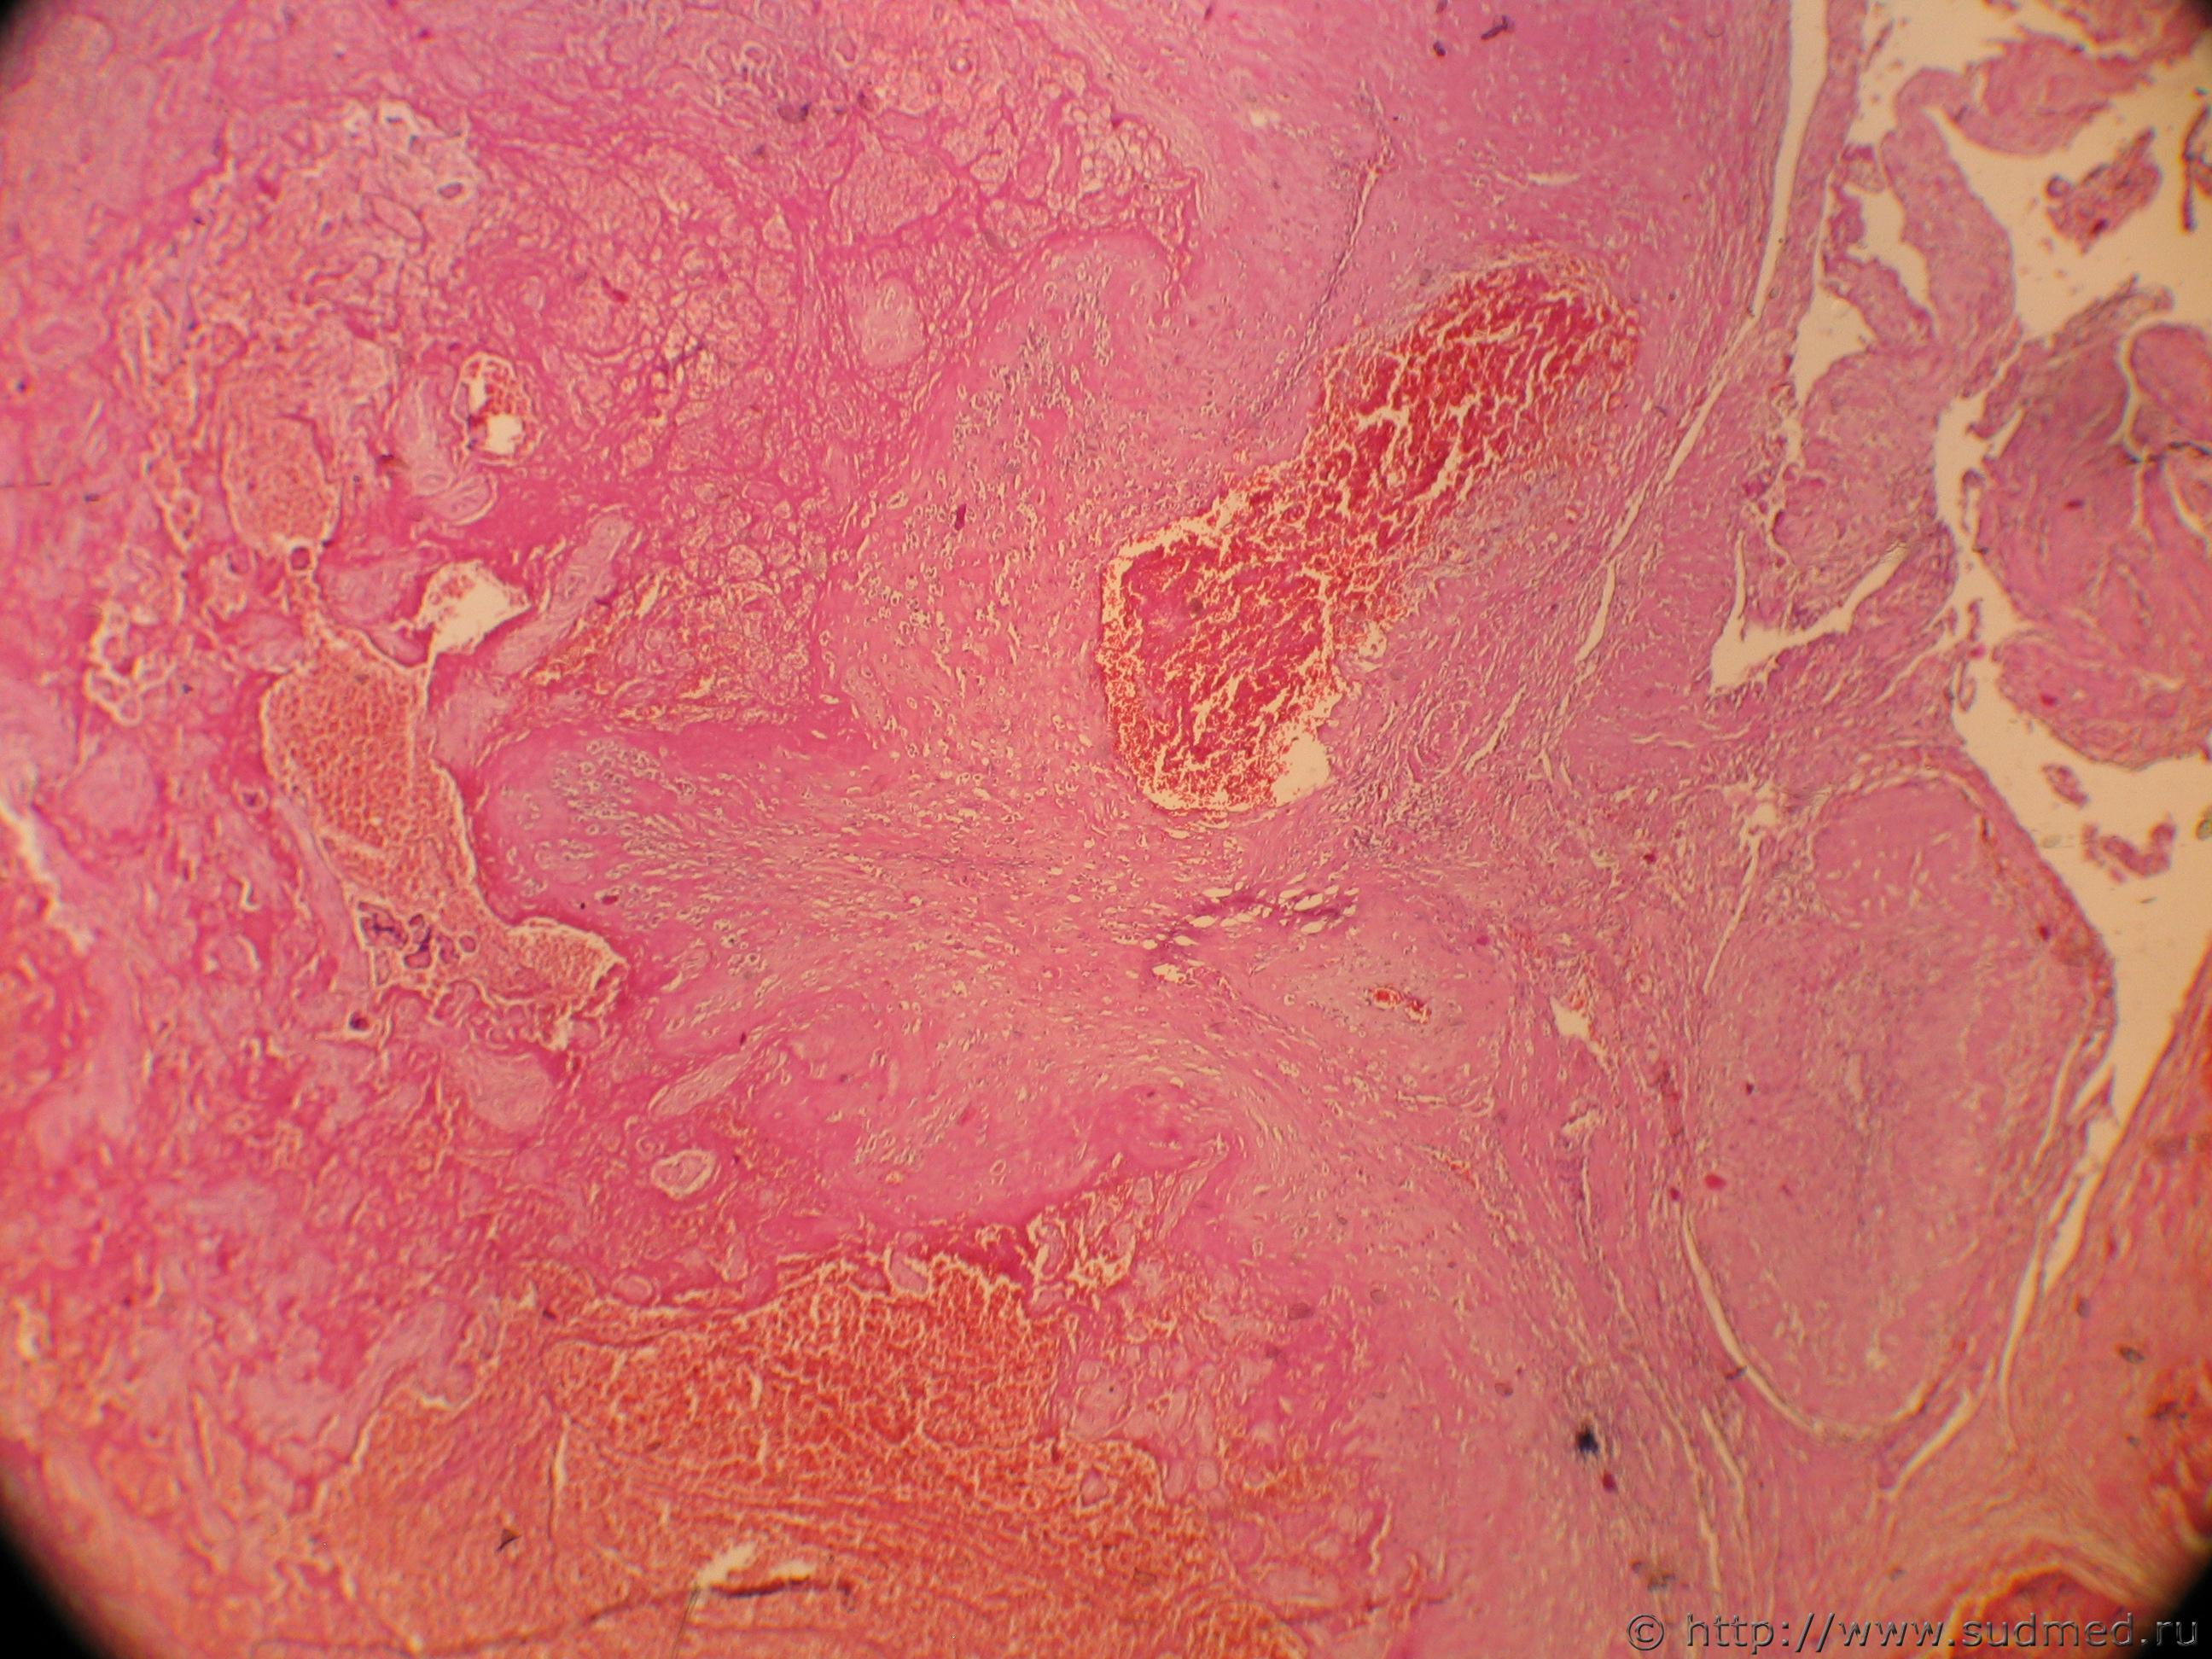

Как-то была тема в КЦ "Плацентарный полип после родов". Недавно попался случай: экстирпация матки в связи с маточным кровотечением на 16 сутки после кесарева. Исследовали патанатомы, я только стекла пересметриваю. Макроописание:"Матка 12Х10Х6 см полость м-ки вскрыта, расширена, по задней стенке эндометрий представлен рыхлыми темно-серыми полипососочковыми разрастаниями, миометрий местами толщиной 2,5 см (***) структуры с очаговыми кровоизлияниями. Микроописание с ним я немного несогласен. Вот фото, если понадобится еще сделаю.

Фото 1: Вместо эндометрия некрозы, крововизлияния, тромбоз сосудов, кое-где с некрозом сосудистых стенок, лейкоцитарные инфильтраты и гиалинизированные ворсины хориона. Фото 2: гиалинизорованная ворсина |